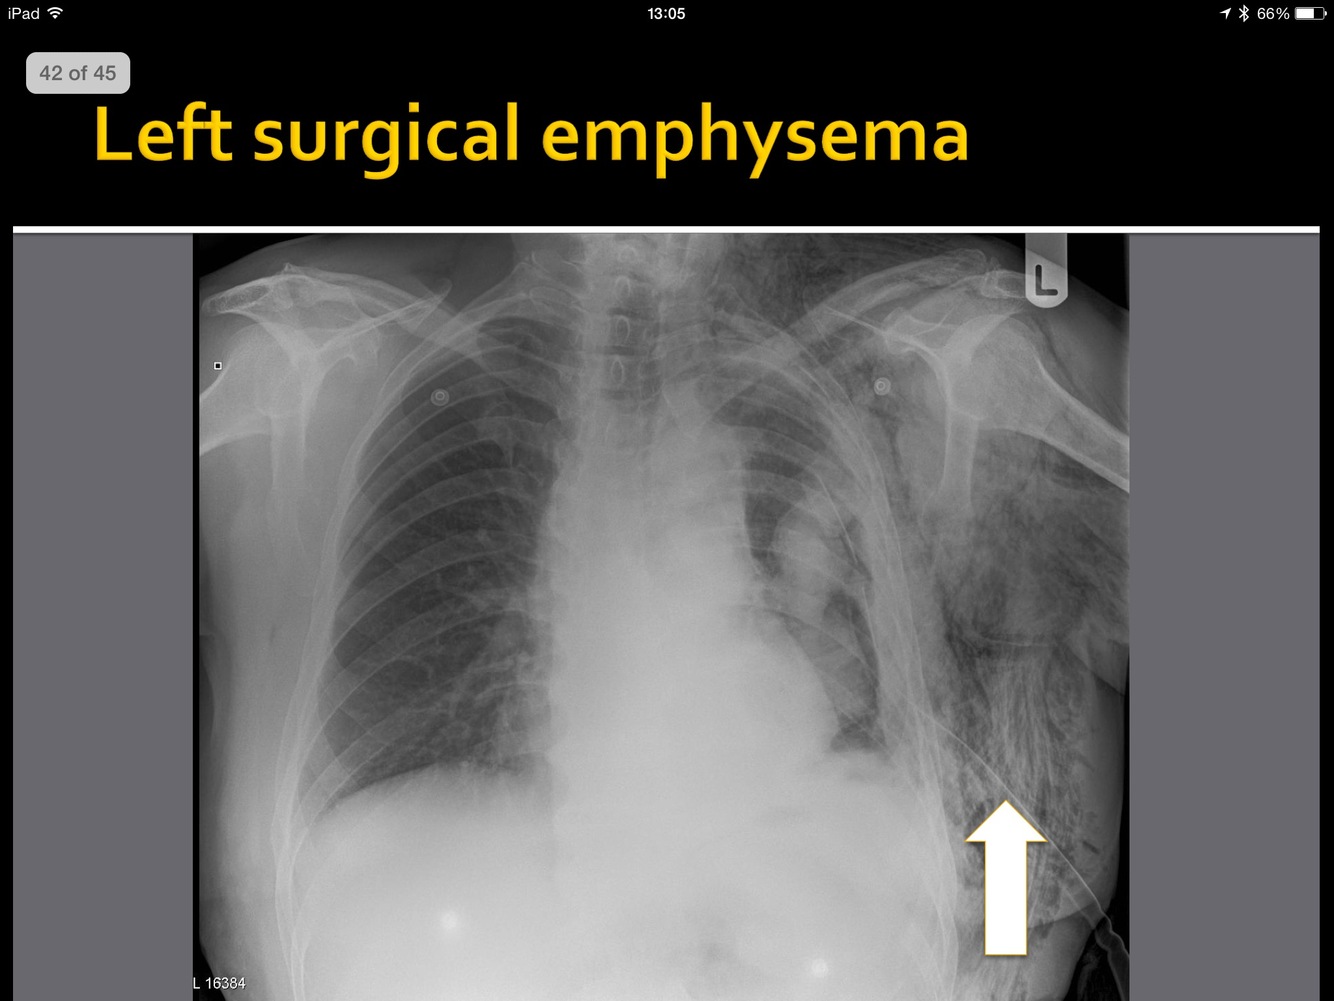

What is the pathology here?